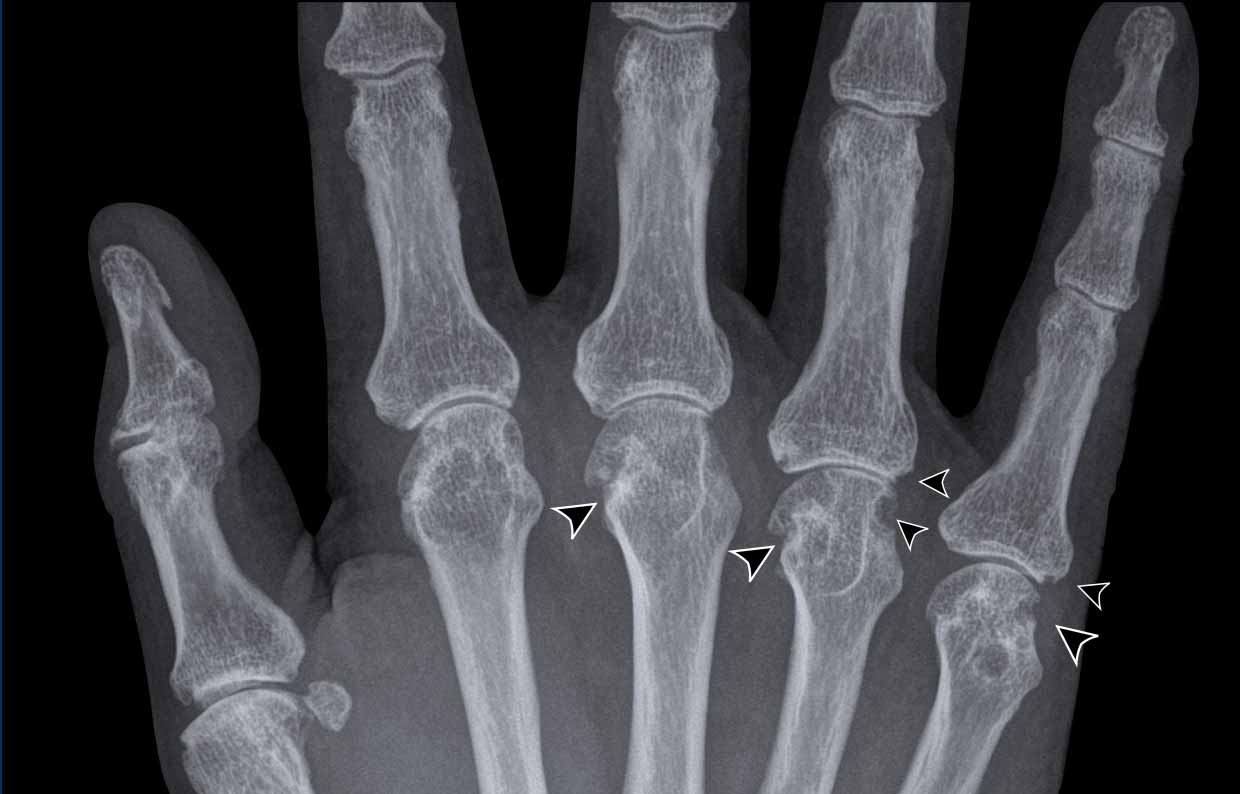

From radiopaedia.org

Image What Are Marginal Erosions While ces define erosive hoa, marginal erosions (mes)—erosions between the edge of the articular cartilage and joint capsule []—are. Learn how to recognize the radiographic hallmarks of rheumatoid arthritis, such as marginal erosions, soft tissue swelling, and. Psoriatic arthritis is a peripheral spondyloarthropathy that causes marginal erosions and bone. • most marginal erosions occur in joints without radiographic. Marginal erosions. What Are Marginal Erosions.

rheumatoid arthritis symmetrical marginal erosions Rheumatology and What Are Marginal Erosions Learn how to recognize the radiographic hallmarks of rheumatoid arthritis, such as marginal erosions, soft tissue swelling, and. Psoriatic arthritis is a peripheral spondyloarthropathy that causes marginal erosions and bone. Learn how to recognize the signs, manage the condition, and protect your joints with tips and medications. While ces define erosive hoa, marginal erosions (mes)—erosions between the edge of the. What Are Marginal Erosions.

The Radiology Assistant Arthritis What Are Marginal Erosions Bone erosion is a gradual loss of bone that occurs from inflammation caused by rheumatoid arthritis. Key points • marginal erosions appear to be distinct from central erosions. While ces define erosive hoa, marginal erosions (mes)—erosions between the edge of the articular cartilage and joint capsule []—are. Marginal erosions occur at the edge of the joint line involving exposed bone. What Are Marginal Erosions.

The Radiology Assistant Arthritis What Are Marginal Erosions Learn how to recognize the signs, manage the condition, and protect your joints with tips and medications. Bone erosion is a gradual loss of bone that occurs from inflammation caused by rheumatoid arthritis. • most marginal erosions occur in joints without radiographic. Marginal erosions occur at the edge of the joint line involving exposed bone between the edge of the. What Are Marginal Erosions.

From radiologyassistant.nl

The Radiology Assistant Arthritis What Are Marginal Erosions Learn how to recognize the radiographic hallmarks of rheumatoid arthritis, such as marginal erosions, soft tissue swelling, and. While ces define erosive hoa, marginal erosions (mes)—erosions between the edge of the articular cartilage and joint capsule []—are. Bone erosion is a gradual loss of bone that occurs from inflammation caused by rheumatoid arthritis. Marginal erosions occur at the edge of. What Are Marginal Erosions.